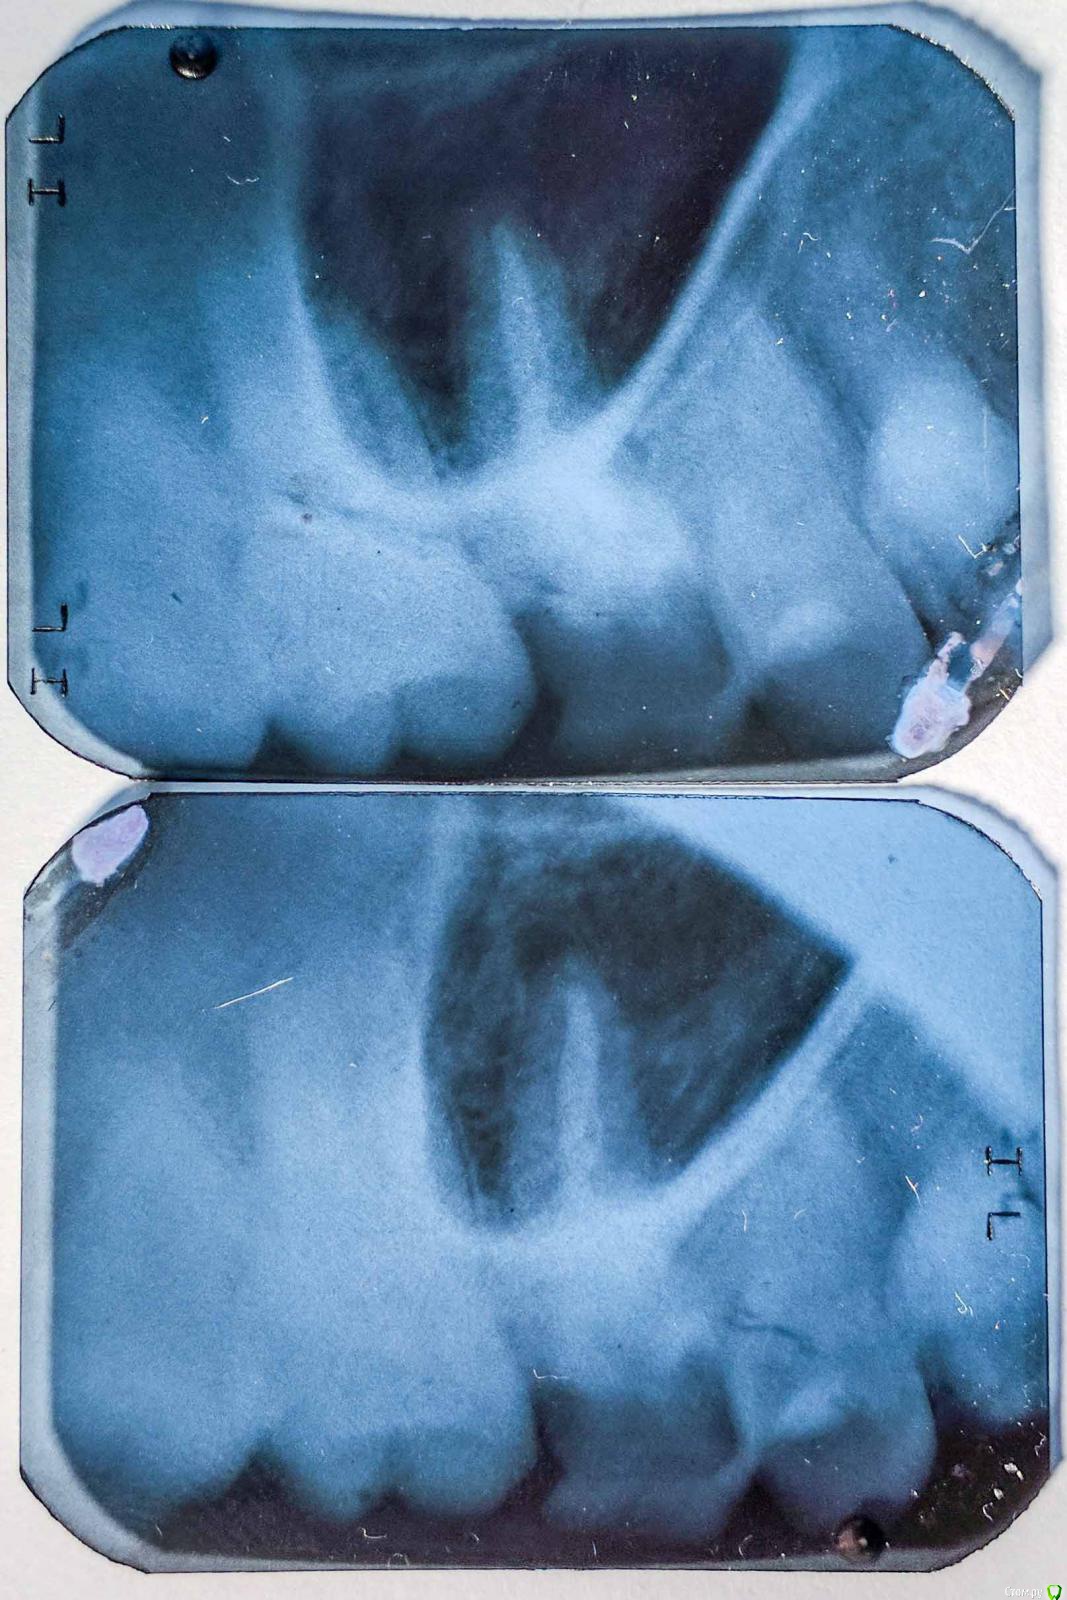

Баурсак Опубликовано 27 июня, 2017 Поделиться Опубликовано 27 июня, 2017 Здравствуйте, прошу помощи.Панарамный снимок сделан 14.04.2017, при планировании лечения зуба 25 (стоит пломба, чувствительность к холодному и горячему).Лечить еще не ходил и вот только собираюсь.Для надежности сегодня сходил и сделал снимки отдельных зубов, того же 25 и еще 16 (тоже планируется лечение, зуб мертвый и начал крошиться).На одиночном снимке зуба 16 видна какая то темная область (снимали его два раза для исключения ошибки). Я очень переживаю, на апрельском снимке темной зоны не видно. Десна в том месте не болит, зуб 16 потемневший, рядом с десной имеет темное обрамление.Подскажите пожалуйста что на снимке? Ссылка на комментарий

shishok Опубликовано 27 июня, 2017 Поделиться Опубликовано 27 июня, 2017 На отдельных снимках наслаивается проекция гайморовой пазухи. Ссылка на комментарий